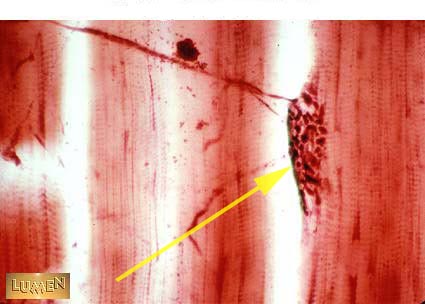

What part of the spinal cord are multipolar motor neuron cell bodies located?

Anterior horn of the spinal cord.